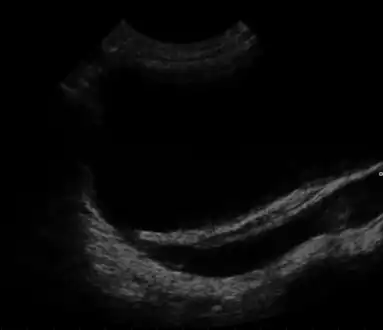

![]() | |

| Ultrasound image showing abnormal vesicoureteral junction and dilated distal ureter resulting in primary vesicoureteral reflux. | |